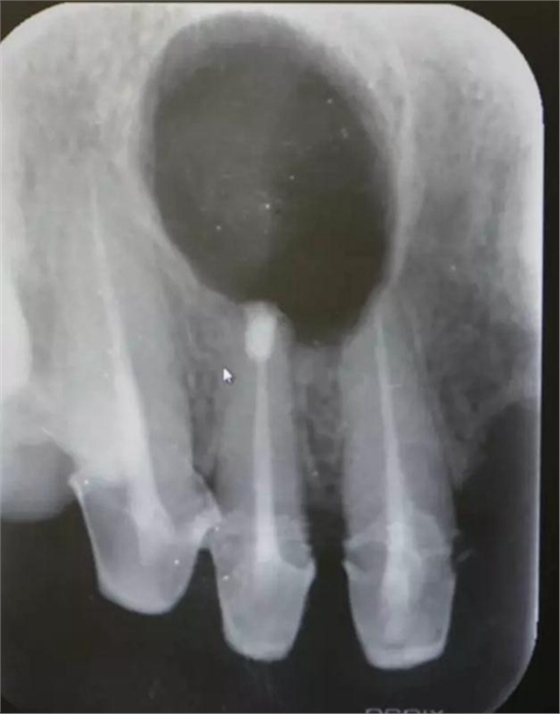

患者、王xx、女、56歲。主訴:右側(cè)上顎部反復(fù)腫痛兩年。專科檢查:上半口烤瓷橋修復(fù),12腭側(cè)隆起,捫診有輕微觸痛。X光:12根尖有圓形規(guī)則陰影,范圍月、約1.0x1.2cm,邊界清晰,11、12根管治療不完善。診斷:12根尖囊腫。治療計劃:1.行11、12根管治療術(shù)。2.擇期行根尖手術(shù)?;颊咄庵委煼桨福炛橥鈺?。

圖1.術(shù)前的根尖片影像檢查:11、12根管治療不完善